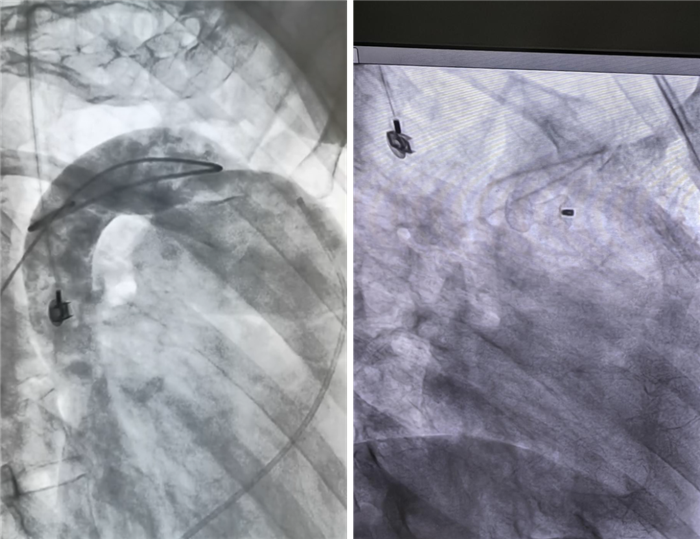

8月30日,经过充分的术前准备,患者在介入导管室接受右心导管检查、动脉导管未闭封堵术。在我院心血管内科医师朱永彪主任的带领下,心血管内科团队互相配合,穿刺、造影、建立轨道、释放封堵器等操作一气呵成,手术顺利完成。术后听诊杂音完全消失,超声检测未见残余分流。